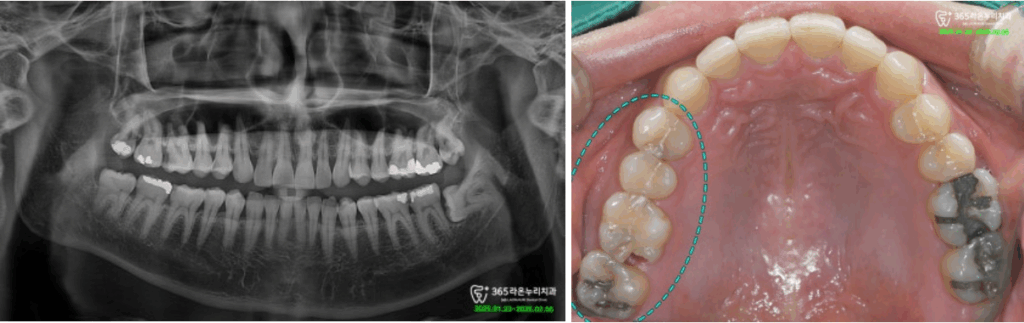

엑스레이 및 구내 포토를

통해 치아의 상태를 정확히

진단하고 파악했는데요.

진단 결과, 인접면 (옆면) 부위에

광활한 충치를 발견할 수 있었습니다.

그런데, 한 쪽 뿐만 아니라 다발성

인접면 우식이 관찰되었습니다.